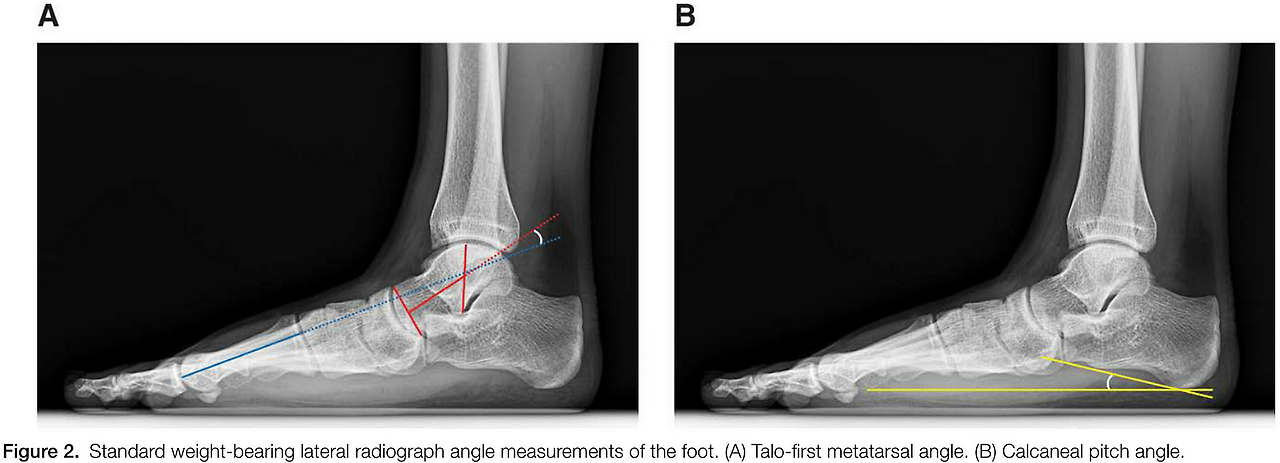

- 거골-중족골 각도(TMA): 정상 -6°~6°, 경도 평발 6°~15°, 중등도-중증 평발 15° 이상

- 종골 경사각(CPA): 정상 17°~25°, 경도 평발 10°~17°, 중등도-중증 평발 10° 미만

1*0PVXmjKMrWZmU375VJfK1A.png 그림 1. 거골-중족골 각도(A)와 종골경사각(B) 측정 예시